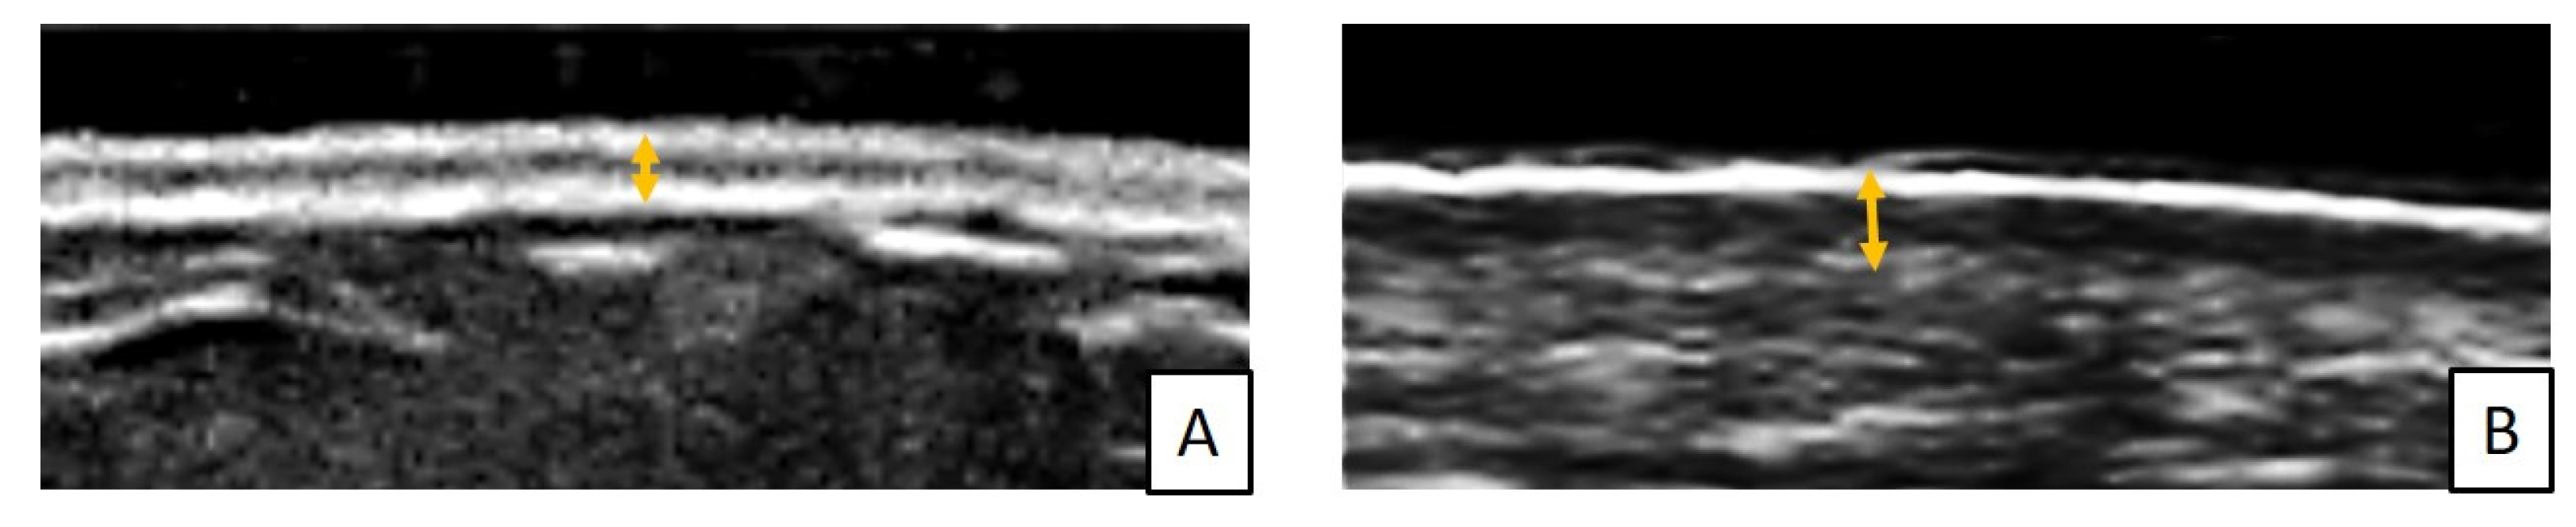

- Santiago, T.; Santos, E.; Ruaro, B.; Lepri, G.; Green, L.; Wildt, M.; Watanabe, S.; Lescoat, A.; Hesselstrand, R.; Galdo, F.D.; et al. Ultrasound and elastography in the assessment of skin involvement in systemic sclerosis: A systematic literature review focusing on validation and standardization—WSF Skin Ultrasound Group. Semin. Arthritis Rheum. 2022, 52, 151954. [Google Scholar] [CrossRef]

- Ruaro, B.; Sulli, A.; Smith, V.; Santiago, T.; da Silva, J.A.P.; Pizzorni, C.; Paolino, S.; Alessandri, E.; Cutolo, M. The impact of transducer frequency in ultrasound evaluation of subclinical skin involvement in limited cutaneous systemic sclerosis patients. Clin. Exp. Rheumatol. 2019, 37, 147–148. [Google Scholar]